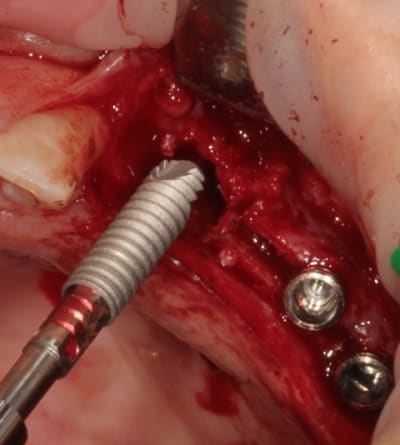

mise en place du conique lisse

L'outil de CLIO

contrôle, axe et profondeur

et un et deux et trois

D1 pour "assouplir"

après les implants lisses coniques il faut passer aux lisses Axioms

donc Ostéotomes impactés pour mettre la corticale du sinus aux dimensions et pousser la membrane (et l'éponge)

en 25 pour le moment l'axiom lisse est de 3.4mm

puis les Axioms avec un 4 mm en 25

retouche de l'os avec le D1 (face plane)

contrôle de l'os vestibulaire (différents contraste pour juger de la "minceur" de l'os :-)))